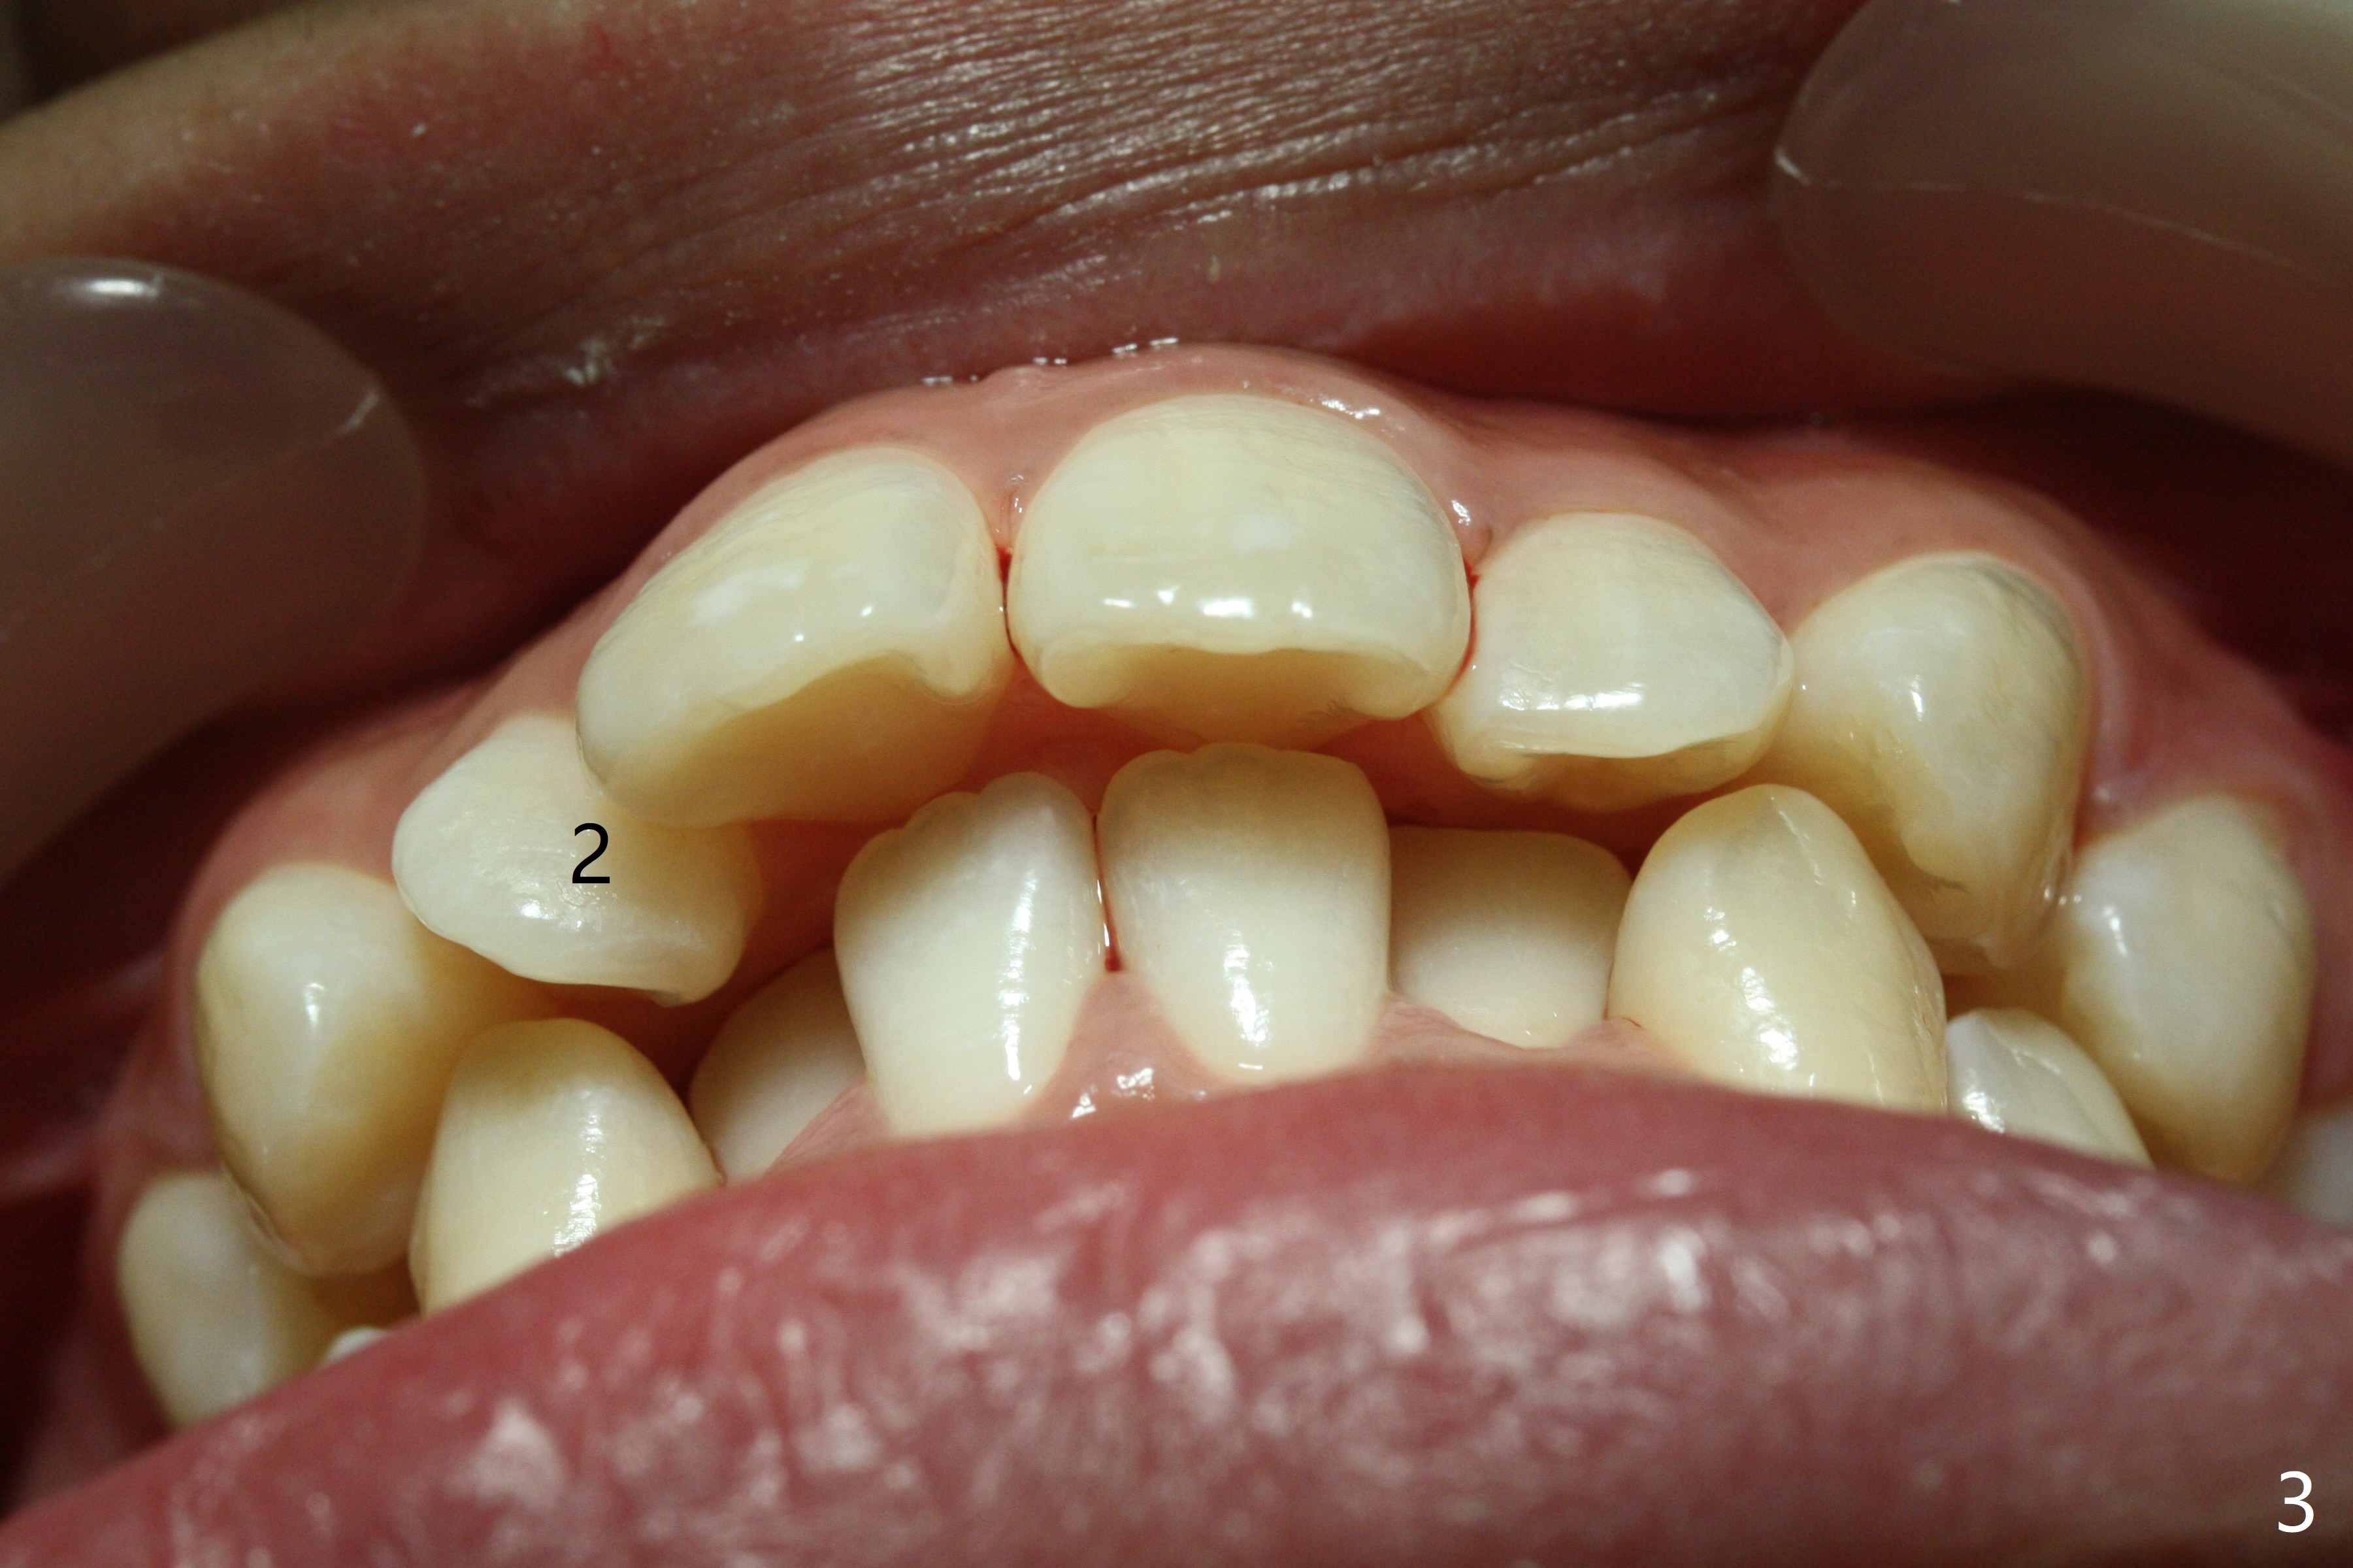

A 17-year-old woman has protrusive lips (Fig.1,2). Due to severe crowding (Fig.3-5), four of the 1st bicuspids are extracted prior to separator placement. It appears that spaces are easier to open up with extraction first. Choose 2nd molar bands with lingual cleats so that 2nd molar cross bite will be corrected immediately post banding (Fig.4,5). Place composite in the occlusal surface of the 1st molars for occlusal separation. Because of severe rotation of UR2, do not place bracket. The same can be applied to L2s. Place power chains x 4 between L3 and 6. The same mechanic will be applied to the right side when R5s are buccalized. Occlusal composite needs to be built up high and several times because of frequent wear, fracturing or detachment (Fig.6 * (1.5 months post banding)).